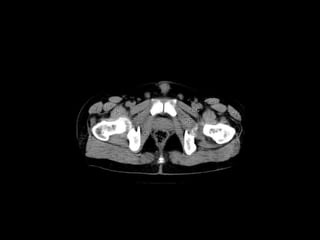

Radiographers use medical imaging equipment like X-rays and MRIs to produce images of patients' internal structures and organs. They are responsible for positioning patients, operating scanning machines, and ensuring quality images. Radiographers must have strong attention to detail, excellent communication skills, and the ability to work well under pressure to accurately capture anatomical features and diagnose any abnormalities.